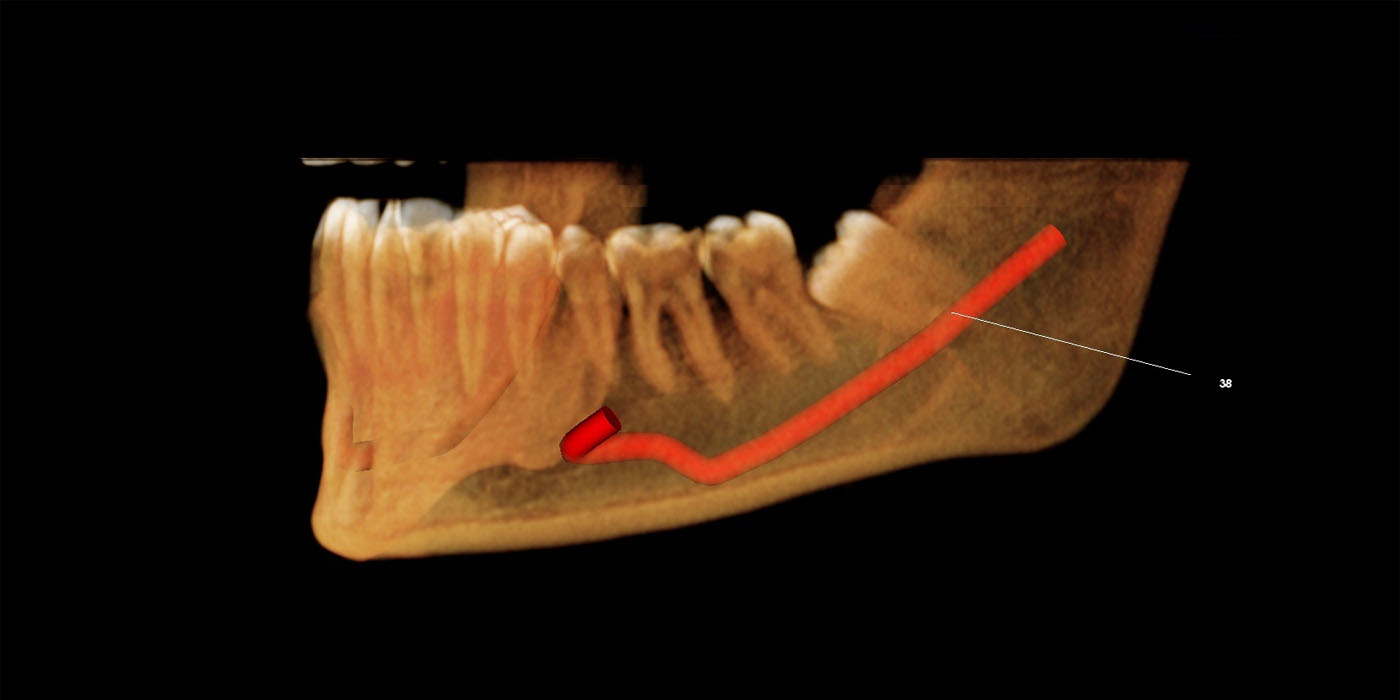

This scan provides full madible evaluation for diganosis and teatment planning for any problem related to mandible, like fracture, cyst, nerve study, imacted tooth, implant evaluation etc.